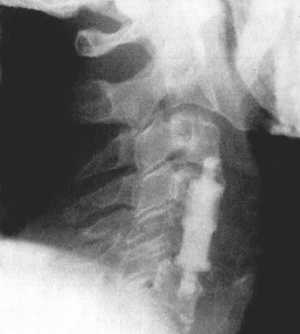

Рис. 3.4. Оскольчатый перелом тела С5-позвонка

до операции и после стабилизации металлическим цилиндром |